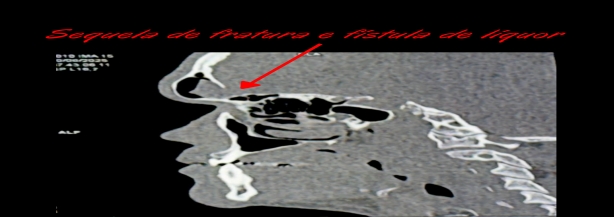

Dentre estas, cito as hidrocefalias pós-traumáticas, fístulas e líquor (líquido que fica dentro do crânio e coluna), alterações infecciosas e deformidades da região do crânio e face.

Para cada uma delas existe um tratamento específico, por isso a necessidade do acompanhamento com um neurocirurgião em casos de TCE é imprescindível.